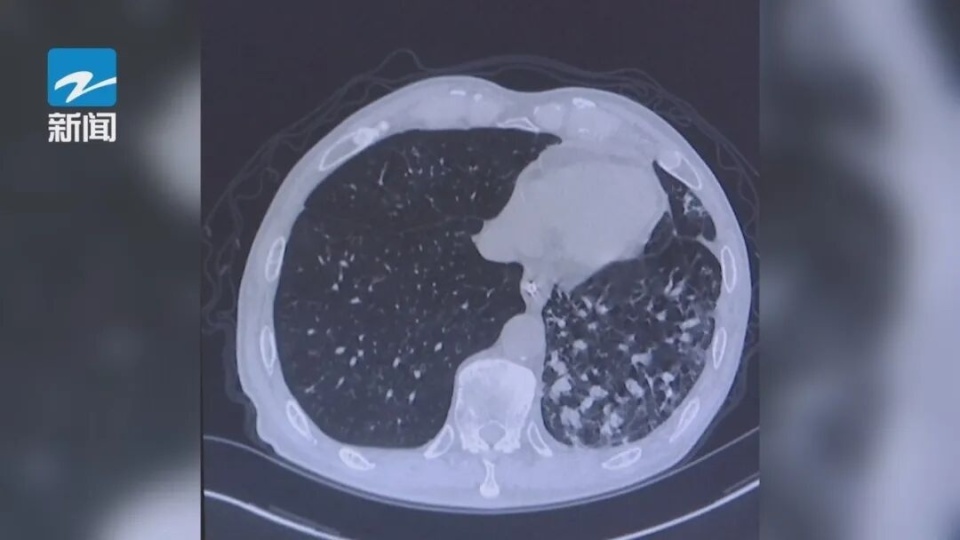

“由于打扫时没戴口罩,扬尘直往嗓子里钻。”林大妈回忆,清扫持续了约五小时,回到家当晚,她就感觉喉咙发痒、胸闷,休息两天后,情况急转直下,体温升至39.5℃,咳嗽剧烈,CT显示大妈双肺有多处斑片状阴影。

血液检测和痰培养最终证实,她感染了曲霉菌和军团菌,病原就隐藏在那些被搅动的“陈年积灰”之中。